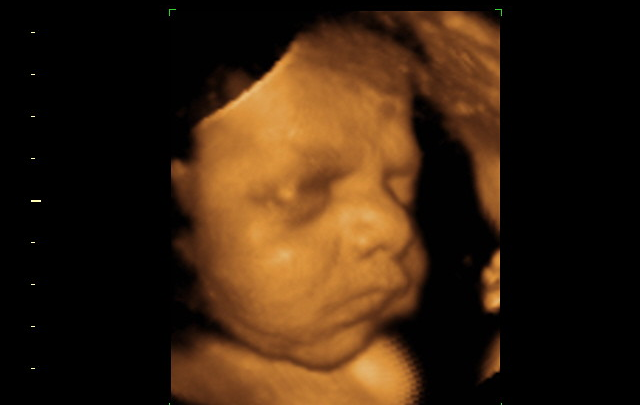

Gains in legal access to abortion are worth celebrating. An analysis between 1994 and 2023 by Katy Mayall and colleagues showed an incredible trend towards the liberalisation of abortion laws across all regions of the world. 825 million women now have access to abortion services who did not before. However, progress has not been uniform. Complete bans on abortion or restrictive laws are concentrated in Africa, Asia, and Latin America, with 97% of unsafe abortions globally concentrated in developing nations. And other barriers exist beyond legality. Mandatory waiting periods and counselling, refusals to provide abortions, harassment and obstruction, and cost can all impede or delay access. Populations marginalised on the basis of race, age, sexuality, and income are typically the most affected and there are strong intersectional and social justice dimensions to abortion access.